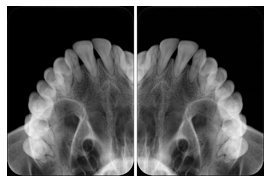

2. A patient requests cosmetic surgery to enhance their facial appearance. The case requires consultation between an orthodontist in New York and an oral surgeon in California. The cephalometric series of 2D projections constructed from the volumetric CT data that is used for the discussion is arranged by a Structured Display for transfer between the two practitioners.

Cephalometric Series Structured Display

Figure OO-2. Cephalometric Series Structured Display